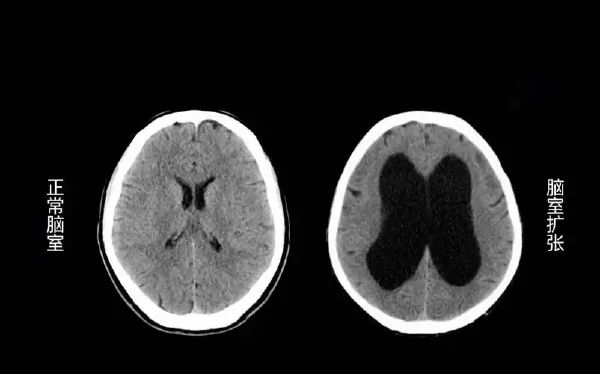

在临床表现上,急性脑积水的症状出现迅速且严重,如剧烈头痛、恶心呕吐和意识障碍等;慢性脑积水则症状出现较为缓慢,早期可能仅表现为头痛、行走不稳、认知功能下降等。为进一步明确脑积水的类型,通常需要进行影像学检查,如头颅CT或MRI。

影像学检查是确诊脑积水的主要手段。头颅CT或MRI可以清晰地显示脑室系统的扩展情况,并帮助识别可能的病因,如肿瘤、出血或畸形等。影像学检查不仅可以确认脑积水的存在,还能帮助判断其类型和严重程度。